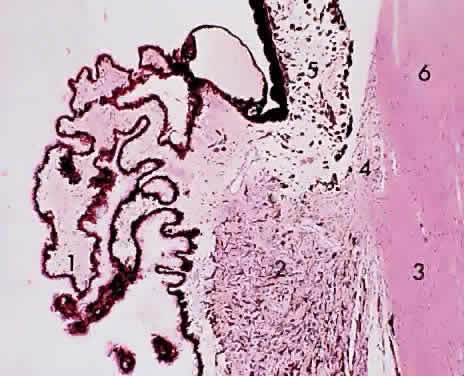

Fig. 13. Pars plana adjoining the retina at the ora serrata: 1, peripheral cystic retina; 2, ora serrata; 3, nonpigmented pars plana epithelium; 4, choroid; 5, sclera (× 225, KEI 8982B).

The pars plana is a 4-mm flat band area extending posterior to the ciliary processes. It joins with the peripheral cystoid retina at the ora serrata (Fig. 13). The nonpigmented epithelial layer flattens anteriorly but becomes columnar posteriorly as it approaches the retina. The pigmented epithelial layer of the pars plana continues as the pigmented epithelium of the retina. A ridged cuticular layer (the reticulum of Muller) lying adjacent to the pigmented epithelium layer of Bruch's membrane at the ora serrata is an avascular connective tissue that separates the inner cuticular layer from the outer elastic layer of Bruch's membrane in the pars plana region (Fig. 14).

The ciliary body is triangular, 6 mm long, with its base abutting the root of the iris and the anterior chamber angle and its apex merging with the choroid and the ora serrata retinae. The ciliary body is commonly described in two sections, the anterior 2 mm (the pars plicata) and the posterior 4 mm (the pars plana). Therefore, surgery on the pars plicata to reduce aqueous secretion should be centered 2 to 3 mm from the limbus, whereas vitreous surgery through the pars plana should be initiated 3.5 to6 mm from the limbus to avoid injury to the lens anteriorly and to the retina posteriorly.